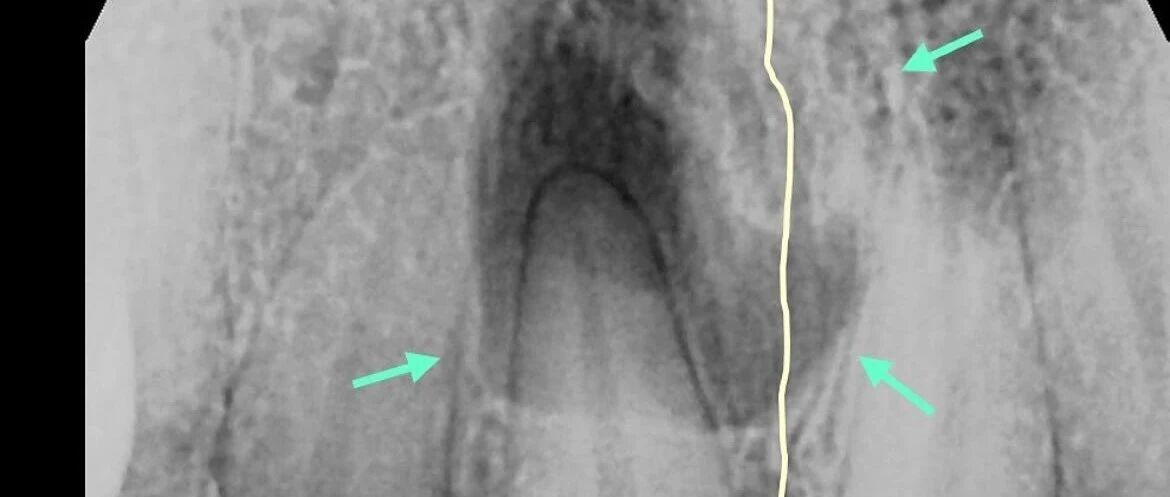

![]() 极易误诊!避免被表面现象误导 口腔医学网 发布时间2026/01/10 23:30:37 | 4 | - | - | 85 | 更多 |